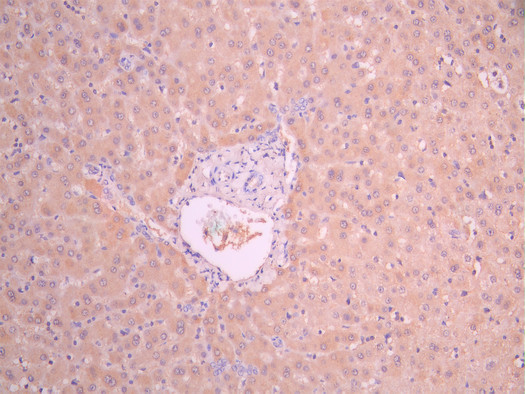

• IHC image of CSB-RA06899MA1HU diluted at 1:50 and staining in paraffin-embedded human liver tissue performed on a Leica BondTM system. After dewaxing and hydration, antigen retrieval was mediated by high pressure in a citrate buffer (pH 6.0). Section was blocked with 10% normal goat serum 30min at RT. Then primary antibody (1% BSA) was incubated at 4°C overnight. The primary is detected by a Anti-Human lgG, Fcy Fragment Specific labeled by HRP and visualized using 0.05% DAB.